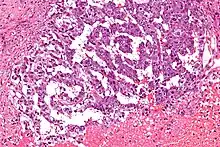

Micrograph showing the yolk sac component of a mixed germ cell tumour. H&E stain.

EST can have a multitude of morphologic patterns including: reticular, endodermal sinus-like, microcystic, papillary, solid, glandular, alveolar, polyvesicular vitelline, enteric and hepatoid.

Schiller–Duval bodies on histology are pathognomonic and seen in the context of the endodermal sinus-like pattern. Rarely, it can be found in the vagina.[6][7]